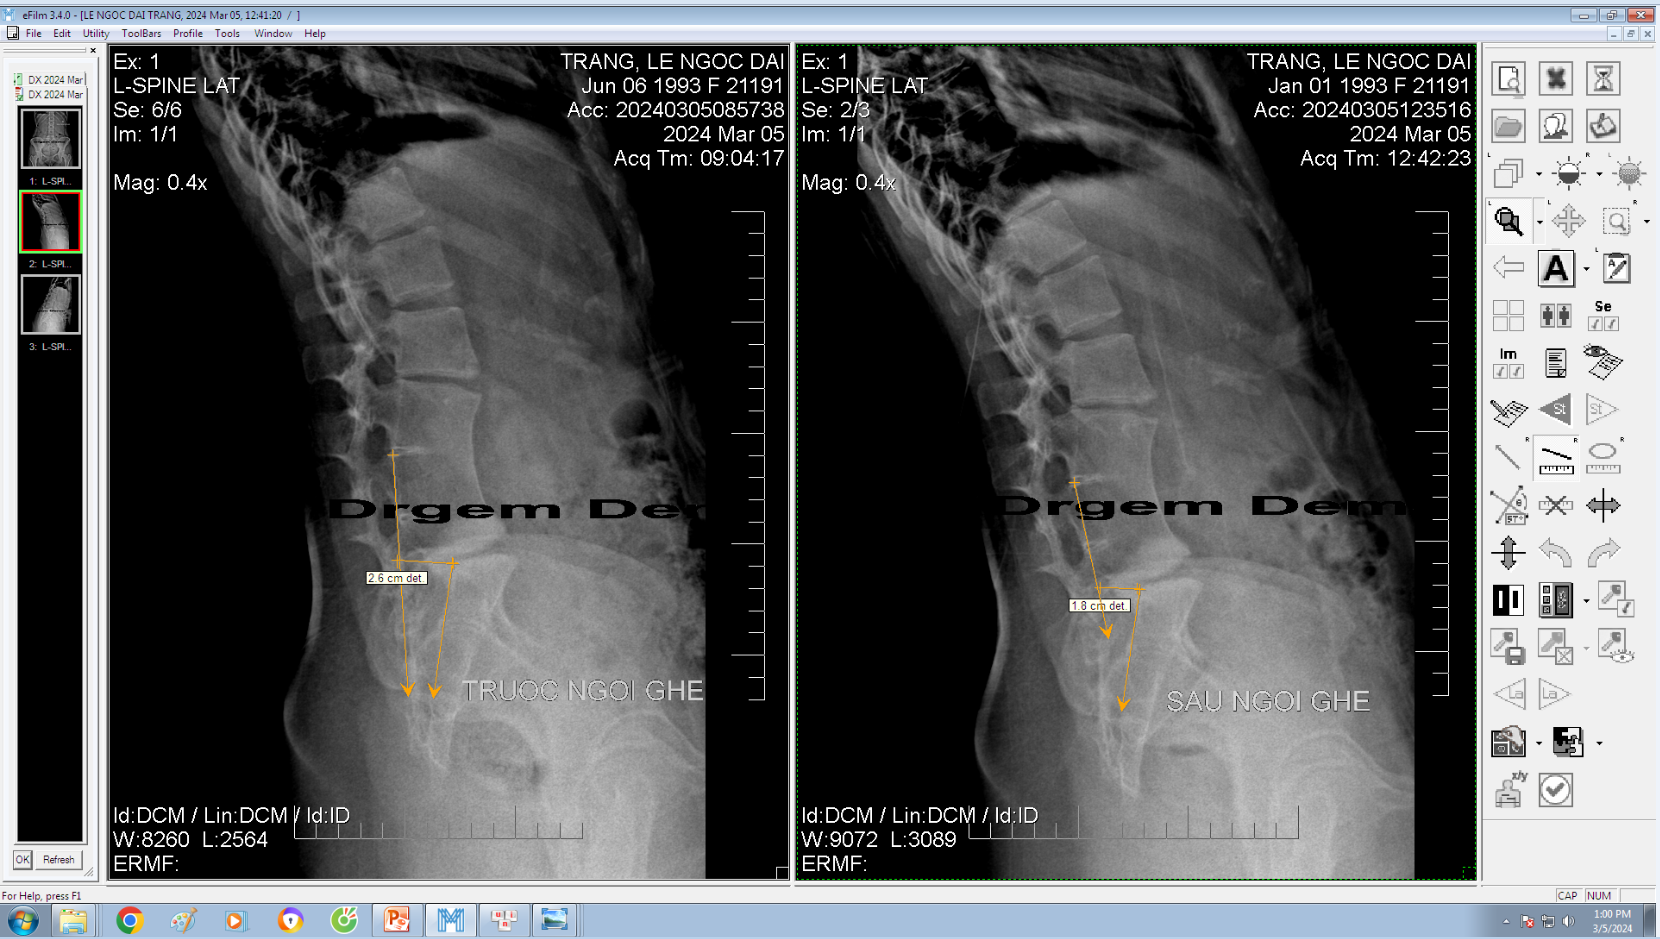

DOCTORLOAN đã thành công trong điều chỉnh xương khớp về đúng vị trí trong thời gian ngắn